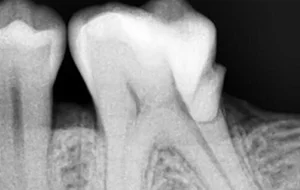

The outer portion or Crown of a tooth is a three-layered structure namely – Enamel, Dentin & Pulp. If the tooth decay is limited to the first two layers, it can be corrected with Filling/ Restoration. In case the tooth decay reaches the third layer and causes inflammation or infection of pulp, an RCT or Endodontic Treatment is needed.

• The very first step involves an X-ray which is taken to determine the extent and approach to infection. If required local anesthesia is administered before starting the treatment.

• The next step is Cavity Preparation. A cavity is prepared, making sure all the infected tooth material or previous filling material is removed and a proper approach to inner-part of the tooth (pulp) is established.